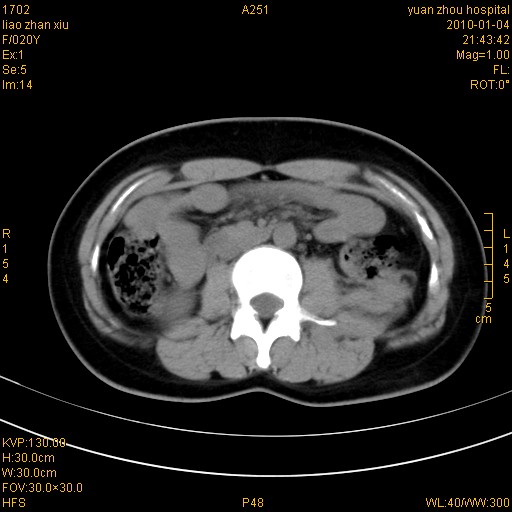

标题: CT23985:F20Y 外伤典型病例

左肾挫伤,包膜下积血。

左肾挫裂伤伴肾被膜下积血!另:肾周筋膜增厚!

1)左肾包膜下血肿。2)左侧肾挫伤可能;建议:行ct增强扫描检查。3)腰椎左侧横突骨折。

左肾挫伤,包膜下积血,l3、4左侧横突多发骨折。

双侧肾胞膜下出血,左侧较多。l3、4左侧横突多发骨折。

1、左肾挫伤,包膜下积血;

2、l3、4左侧横突多发骨折;

3、腹腔积气,考虑肠管破裂?

左肾挫伤,包膜下积血,L1、2、3、4左侧横突多发骨折。